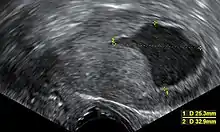

An ultrasound image showing an endometrial fluid accumulation (darker area) in a postmenopausal uterus, a finding that is highly suspicious for endometrial cancer

Vaginal ultrasonography with an endometrial fluid accumulation (darker area) in a postmenopausal uterus, a finding that is highly suspicious for endometrial cancer

Transvaginal ultrasound to examine the endometrial thickness in women with postmenopausal bleeding is increasingly being used to aid in the diagnosis of endometrial cancer in the United States.[39] In the United Kingdom, both an endometrial biopsy and a transvaginal ultrasound used in conjunction are the standard of care for diagnosing endometrial cancer.[15] The homogeneity of the tissue visible on transvaginal ultrasound can help to indicate whether the thickness is cancerous. Ultrasound findings alone are not conclusive in cases of endometrial cancer, so another screening method (for example endometrial biopsy) must be used in conjunction. Other imaging studies are of limited use. CT scans are used for preoperative imaging of tumors that appear advanced on physical exam or have a high-risk subtype (at high risk of metastasis).[40] They can also be used to investigate extrapelvic disease.[15] An MRI can be of some use in determining if the cancer has spread to the cervix or if it is an endocervical adenocarcinoma.[40] MRI is also useful for examining the nearby lymph nodes.[15]